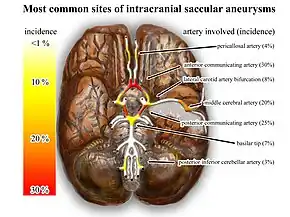

Saccular aneurysms

Saccular aneurysms are almost always the result of hereditary weakness in blood vessels and typically occur within the arteries of the Circle of Willis,[14][16] in order of frequency affecting the following arteries:[17]

- Anterior communicating artery

- Posterior communicating artery

- Middle cerebral artery

- Internal carotid artery

- Tip of basilar artery

Saccular aneurysms tend to have a lack of tunica media and elastic lamina around its dilated location (congenital), with wall of sac made up of thickened hyalinized intima and adventitia.[8] In addition, some parts of the brain vasculature are inherently weak—particularly areas along the Circle of Willis, where small communicating vessels link the main cerebral vessels. These areas are particularly susceptible to saccular aneurysms.[6] Approximately 25% of people have multiple aneurysms, predominantly when there is familial pattern.[7]